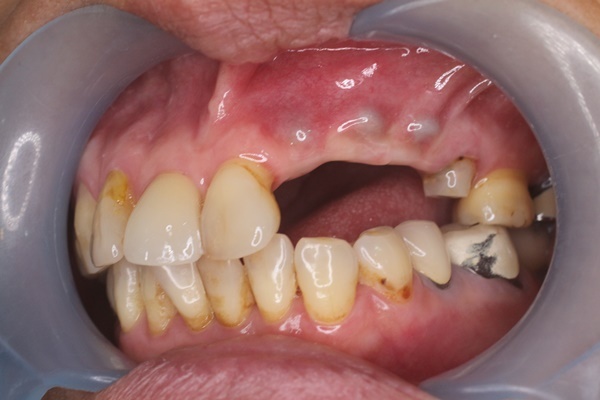

在手術前凌秋蓮醫師有針對我的個人狀況瞭解

他說每個患者身體情況不同

身體的健康與否會影響植體的恢復期

植牙前凌秋蓮醫師會做身體健康飲食建議

針對患者身體狀況及需求,建議植牙期間專屬患者飲食的指南。

讓糖尿病、高血壓、骨質疏鬆、等患者在做植牙時身體狀態無慮再安排做植牙,

在植牙前還會透過 2d 或 3d 的影像來判讀牙根狀況,

經過醫師建議與費用評估後

我是挑選這一款植體

因為植體植入後傷口還沒有恢復時再不敢拍給大家看

等後面恢復好一些再來跟大家分享後續植牙過程